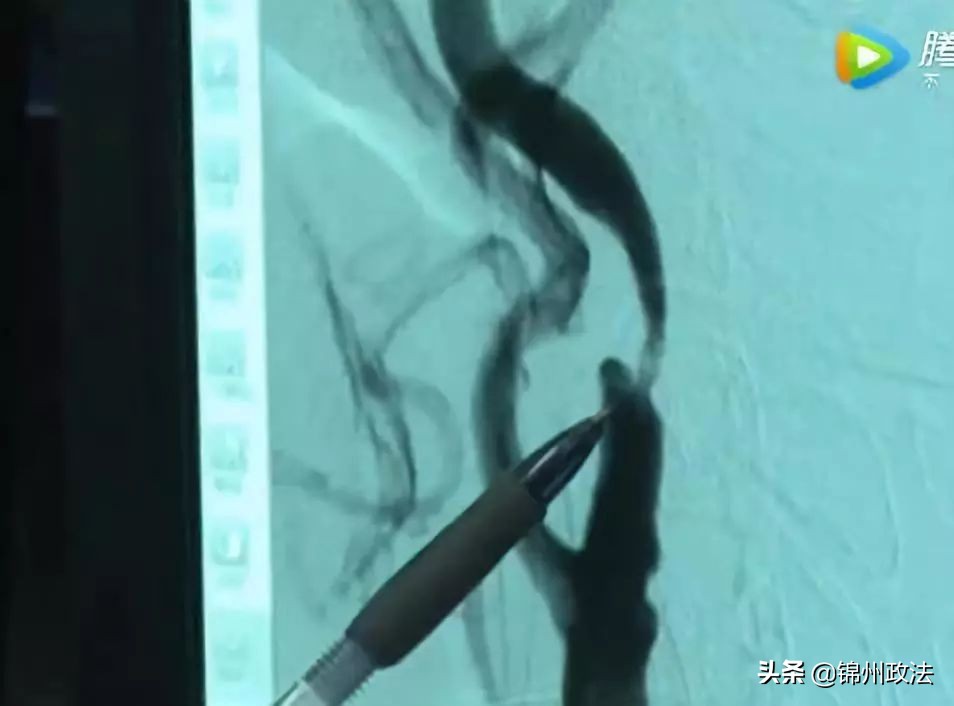

考虑到患者左脑的缺血性症状更加明显,吴杰团队率先为患者实施了左侧颈内动脉剥脱术,顺利“掏”出一块长约2cm的黄色油脂。术后,张大叔右侧肢体逐渐恢复了力量。

为预防右侧颈动脉内的斑块随时脱落,并随血液上行堵住脑血管,造成缺血性脑中风,12月初,张大叔按医生的叮嘱再次来到了广东三九脑科医院。吴杰团队为患者实施了右侧颈内动脉剥脱术。

手术过程中,吴杰小心翼翼地分离患者的血管,把颈动脉内膜上一块长约3cm的黄色斑块完整“掏”出,并彻底清除了残留的碎片和斑块碎屑。